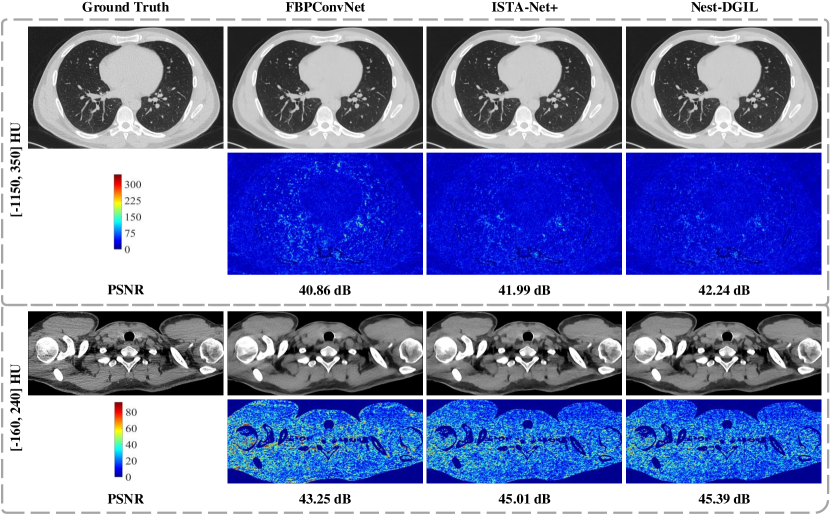

Sparse-view CT: To further demonstrate the superiority of our approach, we perform a group of comparisons to evaluate the reconstruction performance in sparse-view CT. We compare our method with classical methods (FBP, FISTA-TV [52]), deep learning method (RED-CNN [71], FBPConvNet [25], DU-GAN [72], Deep Decoder [27]) and state-of-the-art deep unfolding methods (PD-Net [34], ISTA-Net [30], ISTA-Net+ [30], FISTA-Net [7], AMP-Net-K [31]). The FBP with the ”Ram-Lak” filter, which is implemented with the iradon transform in TorchRadon [67], is adopted to provide initialization for the proposed method and other compared deep models. The maximum number of iterations of FISTA-TV is set as 100 and the regularization parameter is tuned to optimal. Following [7], the stage numbers of PD-Net, ISTA-Net, ISTA-Net +, FISTA-Net, AMP-Net-K, and Nest-DGIL are configured as 7. The number of iterations of the deep decoder is set to 2000 [27].

Table IV lists the average PSNR and RMSE (HU) of the compared methods with different down-sampled projection views. We can observe that ISTA-Net and ISTA-Net+ consistently outperform FISTA-Net for all downsampled projections due to unshared learnable parameters. Due to abundant learnable parameters and considerable training data, RED-CNN and FBPConvNet achieve a good reconstruction performance. Due to underparameterization and without checking the data consistency with the measurement, the Deep Decoder cannot reconstruct the CT image well. Our method outperforms comparison methods at all down-sampled projections and achieves an average 0.17 dB improvement on LDCT-Data and an average 0.18 dB improvement on FRPLung-Data. In addition, our method can obtain a more accurate HU reconstruction and provide a better service for clinician diagnosis.

The results of axial reconstruction from different methods for parallel beam projection with 60 views are shown in Fig.8. FBPConvNet can remove streak artifacts effectively, but some tiny structures could be smoothed out. Although ISTA-Net+ can remove some noise and streaking artifacts, but results in incomplete preservation of details and texture information. Due to cascade geometric incremental learning and adaptive remainder optimization, our method achieves the best reconstruction performance in terms of noise artifact removal and detail preservation (e.g., tiny blood vessels and bronchi).